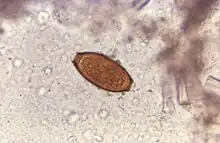

The disease is usually spread when people eat food or drink water that contains the eggs of these worms.[2] This may occur when contaminated vegetables are not fully cleaned or cooked.[2] Often these eggs are in the soil in areas where people defecate outside and where untreated human feces is used as fertilizer.[3] These eggs originate from the feces of infected people.[2] Young children playing in such soil and putting their hands in their mouths also become infected easily.[2] The worms live in the large bowel and are about four centimetres in length.[3] Whipworm is diagnosed by seeing the eggs when examining the stool with a microscope.[4] Eggs are barrel-shaped.[9] Trichuriasis belongs to the group of soil-transmitted helminthiases.[10]

Adult worms are usually 3-5 cm long, with females being larger than males as is typical of nematodes. The thin, clear majority of the body is the esophagus, and it is the end that the worm threads into the mucosa of the colon. The widened, pinkish gray region of the body is the posterior, and it is the end that contains the parasite's intestines and reproductive organs. T. trichiura eggs are prolate spheroids, the shape of the balls used in Rugby and Gridiron football.[32][14]

A stool ova and parasites exam reveals the presence of typical whipworm eggs. Typically, the Kato-Katz thick-smear technique is used for identification of the Trichuris trichiura eggs in the stool sample.Although colonoscopy is not typically used for diagnosis, as the adult worms can be overlooked, especially with imperfect colon, there have been reported cases in which colonoscopy has revealed adult worms. Colonoscopy can directly diagnose trichuriasis by identification of the threadlike form of worms with an attenuated, whip-like end. Colonoscopy has been shown to be a useful diagnostic tool, especially in patients infected with only a few male worms and with no eggs presenting in the stool sample.[14][33][34][13]